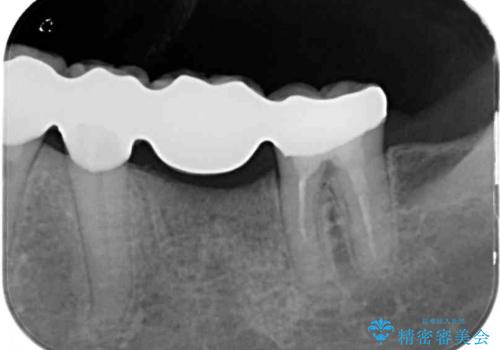

治療開始の日に欠損部も含めて仮歯が装着され、今までの不具合や不快感があっという間に改善されました。

抜歯部位の治癒を待つために時間がかかりましたが、来院回数は数回で済み、患者様には大変満足していただきました。